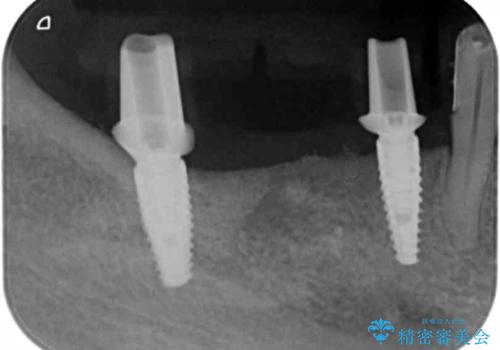

残すことのできない歯を抜去したのち、骨を造成し安定した環境下で長期的な予後を期待できるインプラント治療を計画します。

- 275万円(インプラント×5・チタンカスタムアバットメント×5・ジルコニアクラウン×7・仮歯×7)費用は治療当時の料金となります